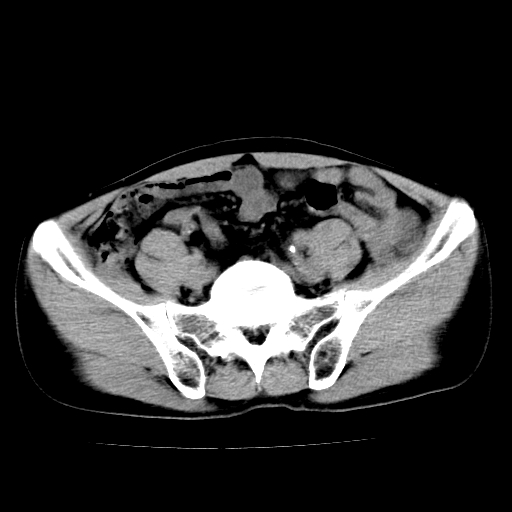

男,47岁,左输尿管结石碎石治疗后10余日。彩超示:左输尿管下段狭窄、输尿管积水。请各位讨论一下左输尿管下段结石还是静脉石?

象是第二狭窄处结石伴以上输尿管、肾盂轻度积水。

输尿管结石伴以上输尿管、肾盂轻度积水。

两侧髂总动脉壁斑状及点状钙化.左侧输尿管行经与左髂总动脉相交后见高密度影,且下段输尿管管腔未见扩张,应该要考虑结石伴以上输尿管及肾盂积水.但右侧结节状高密度影,也应该是结石吧!那以上输尿管未见扩张呢!因此静脉结石可能性也较大.请问楼主碎石前左侧输尿管结石位置.

虽左侧有轻度肾盂积水但不支持结石。1结石边周应该有软组织包绕呈晕征。2钙化点前面见输尿管影也不支持是结石。3彩超没提结石。建议超生复查。

输尿管先位于腹部,后进入盆腔,最后斜穿膀胱壁开口于膀胱,因此,临床上常将输尿管分为腹段、盆段和壁内段。第1个狭窄:在肾盂与输尿管移行处。第2个狭窄:在跨过髂血管处。第3个狭窄:在穿过膀胱壁处。这些狭窄是结石容易滞留的部位。

左侧输尿管有轻度扩张伴有肾盂积水,输尿管下段周围的高密度影不象在输尿管内。

同意,不支持结石。(因显示该高密度影前见扩张输尿管影,另外两侧对称显示)。

左侧高密度影在左侧输尿管的内侧方,所以不考虑输尿管结石.

我认为不是结石的可能性大,因为他的位置和血管钙化的位置邻近